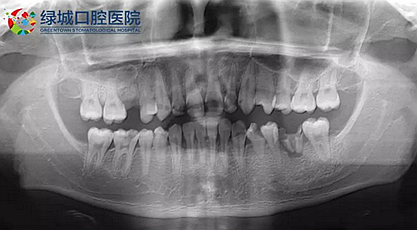

下面是醫(yī)生眼中和ct下的我們

一身病痛啊

牙結(jié)石、牙齦炎癥、牙體殘缺、慢性牙髓炎、蛀牙......

治療是從5月份開始的,醫(yī)生給我的主人驗了血,做手術(shù)前的準(zhǔn)備,還給我們都用超聲波好好的都洗了個澡,把之前依附在我們身上的牙結(jié)石都沖了個干凈(齦上潔治術(shù))。治療先從我和其他3個兄弟開始。在麻藥的作用下,我們兄弟4個都被打開了身體,去除了已經(jīng)被蛀牙破壞的牙體,做了根管治療。